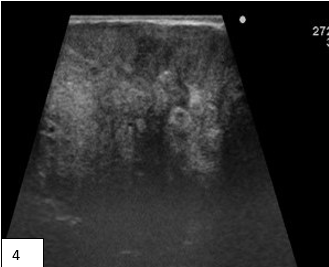

Fig 1a: Ultrasound shows coarse heterogenous liver parenchyma with surface irregularity & nodularity Fig 1b,c,d : CECT Imaging shows Small nodular cirrhotic liver with multi lobulated , well defined masses having mild heterogeneous post-contrast enhancement & few calcific foci in bilateral axilla and inguinal region. Hugely enlarged breasts partly seen in the scan. Ascites present. Fig 2 : 2D mammo (a,b) and Tomo images (c,d) of both breasts show bilateral high density large masses with smooth margins and no architectural distortion however few course heterogenous calcifications present randomly in breast parenchyma. (compromised scan quality is attributed to massive breast size) Fig 3 a,b,c,d : Ultrasound of bilateral breasts show iso to heteroechoic large breast masses occupying almost entire breasts. Normal breast tissue was compressed and difficult to identify. Colour doppler demonstrates significant vascularity within the masses. Fig 4 : Ultrasound of axillary lymph nodes. Fig 5 a,b : Biopsy from breast masses showed amyloid deposits (pink) predominantly around the ducts and blood vessels (a), demonstrated well on congo red stain (b).